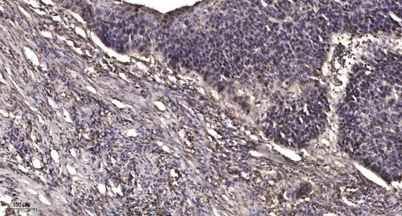

Applications IHC

Recomended Dilution IHC-p 1:50-300